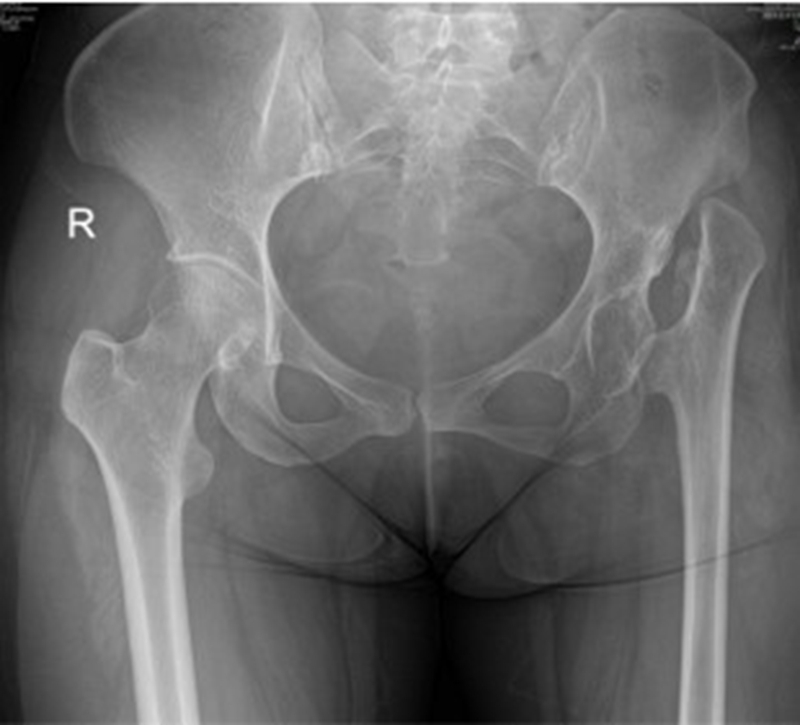

(3)股骨成角畸形

程度轻,且远离假体安放位置:近端固定短柄假体或小号骨水泥型假体。

严重且靠近假体安放位置:必须行截骨矫正,以获得良好的对线。

三、手术策略及处理

手术的核心思想:恢复旋转中心、恢复下肢长度、恢复肌肉张力。

髋关节生物力学中,外展肌作用力尤为重要。故外展肌止点位置——大粗隆是术中需要调整的位置。